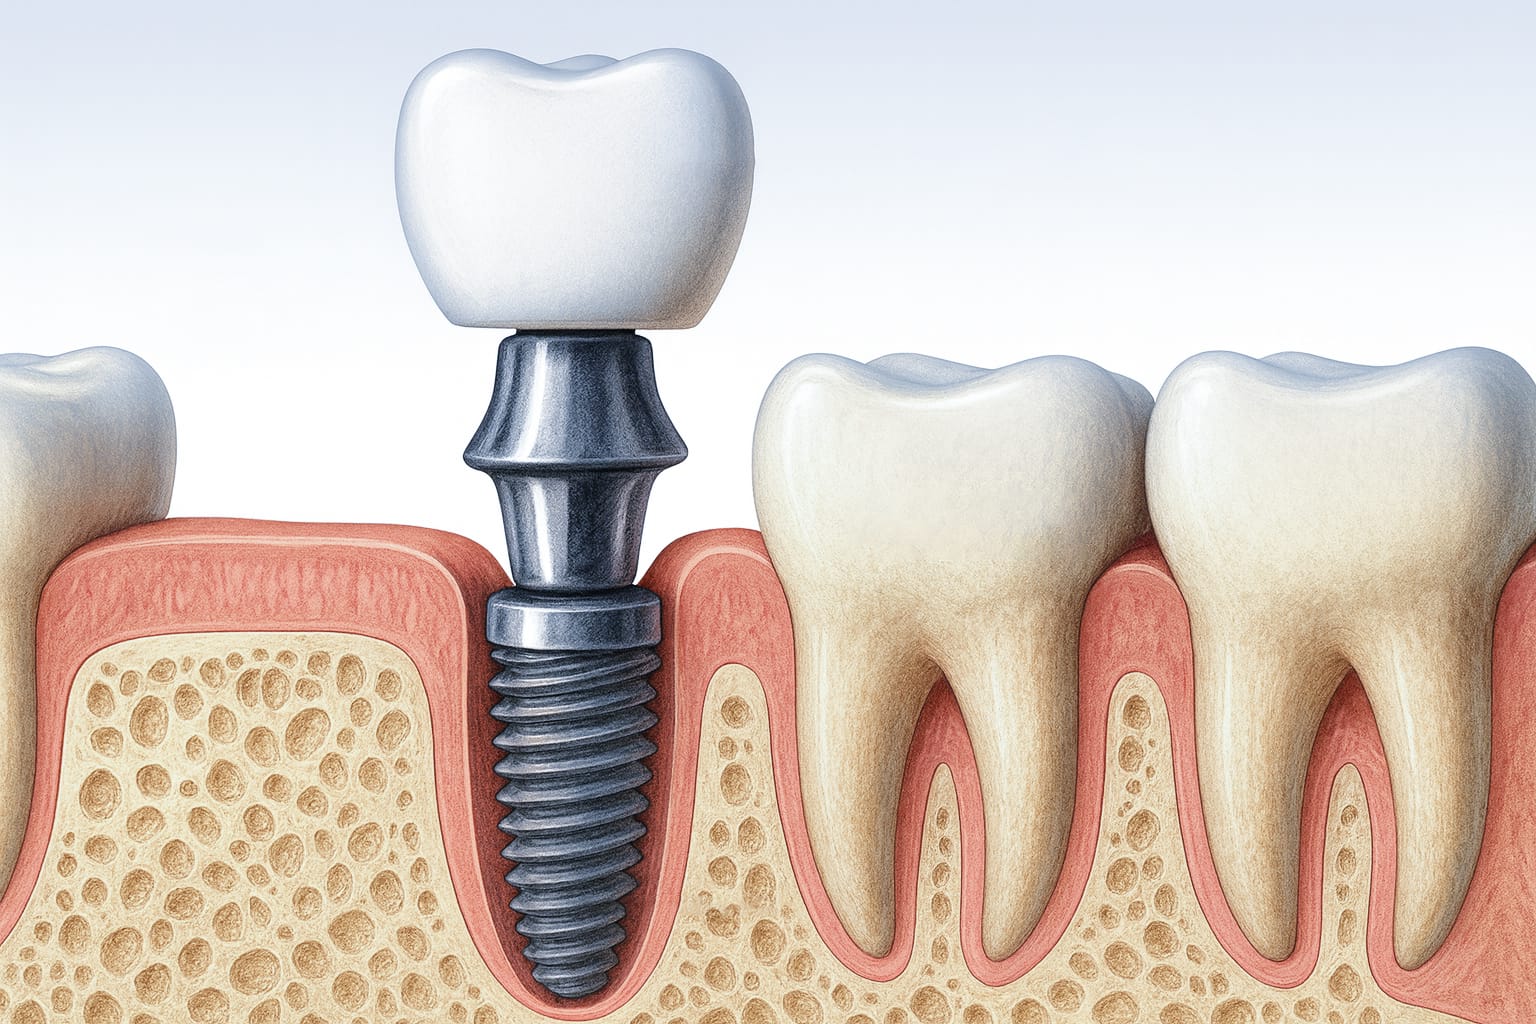

Los implantes dentales son la solución más completa y duradera para reponer dientes ausentes. Consisten en pequeños dispositivos de titanio que se colocan en el hueso maxilar o mandibular, cumpliendo la función de raíz dental. Sobre ellos se fija una corona que devuelve la estética y la función masticatoria de forma permanente.

Sustituye la raíz de una sola pieza dental perdida. Es la opción más frecuente y permite preservar la salud del hueso circundante, evitando que las piezas vecinas se desplacen con el tiempo.